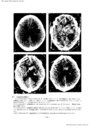

第3脳室近傍腫瘍の神経放射線診断-脳血管撮影を中心に- III 主に第3脳室の側方に発育する腫瘍(1)